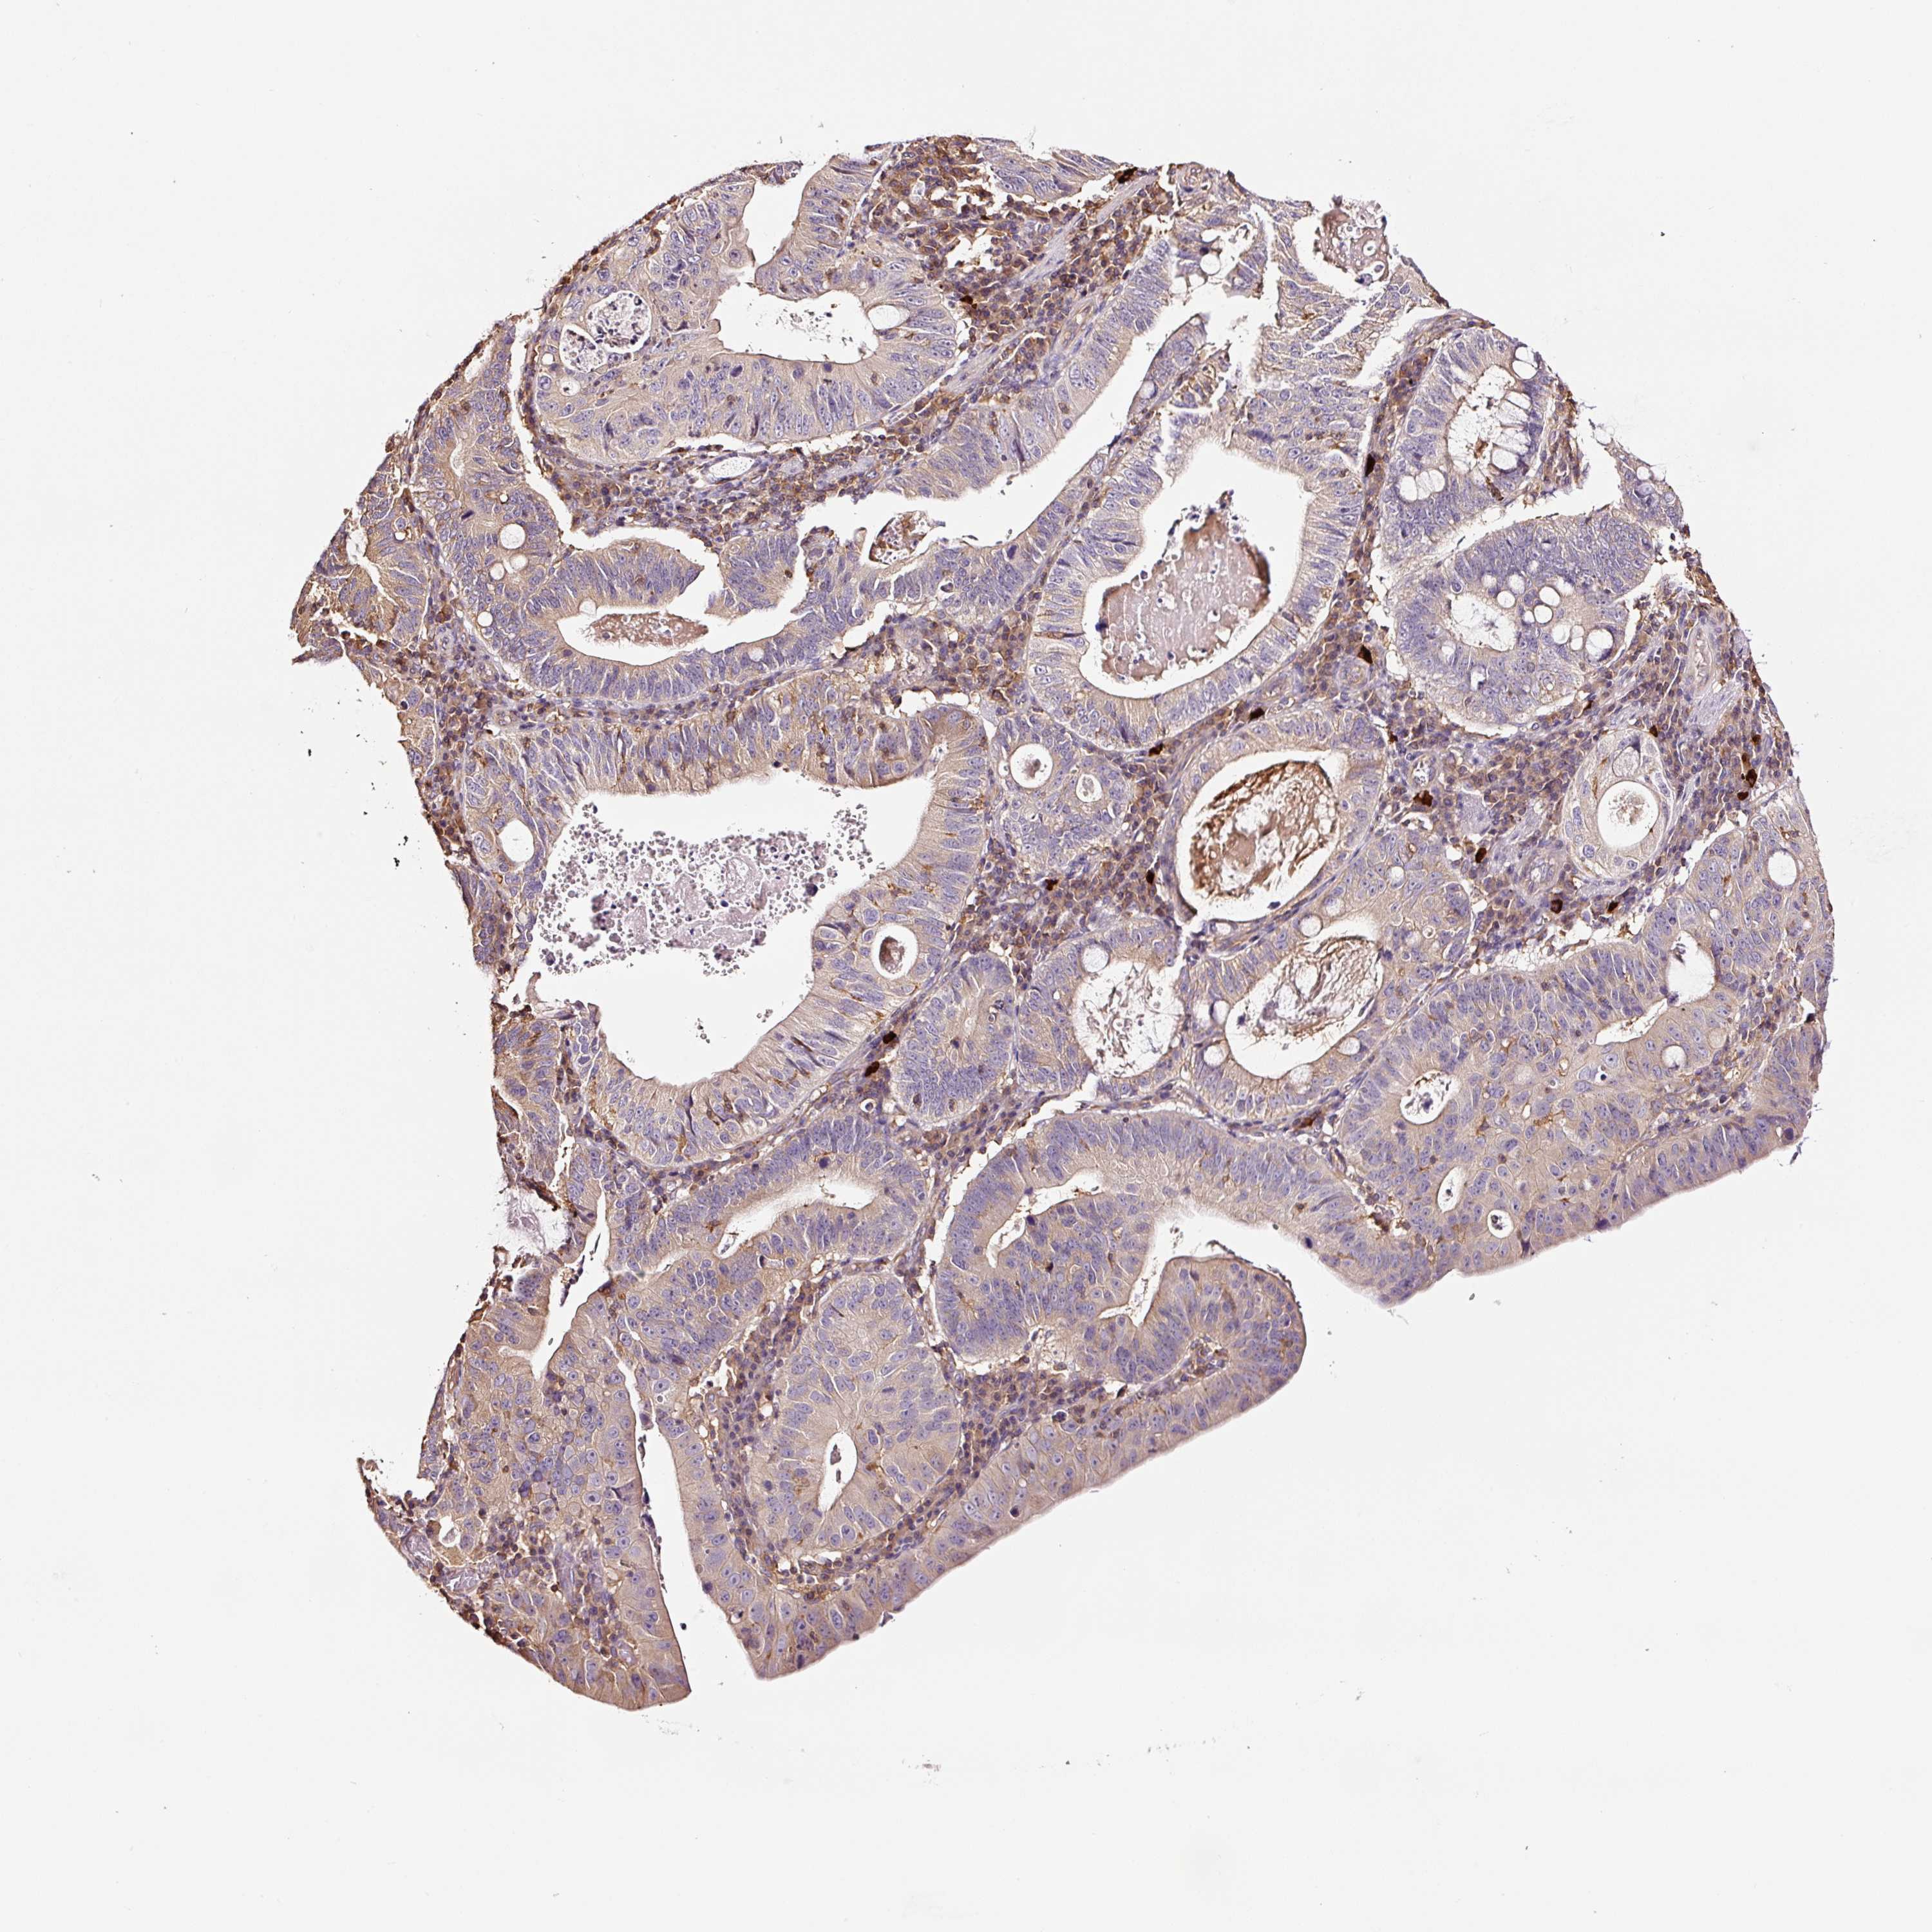

STOMACH CANCER - Protein expressioni

A mouse-over function shows sample information and annotation data. Click on an image to view it in a full screen mode. Samples can be filtered based on level of antibody staining by selecting one or several of the following categories: high, medium, low and not detected. The assay and annotation is described here.

Note that samples used for immunohistochemistry by the Human Protein Atlas do not correspond to samples in the TCGA dataset.

Antibody stainingi

Antibody staining in the annotated cell types in the current human tissue is reported as not detected, low, medium, or high, based on conventional immunohistochemistry profiling in selected tissues. This score is based on the combination of the staining intensity and fraction of stained cells.

Each image is clickable and will lead to virtual microscopy that enables deeper exploration of all samples and also displays staining intensity scores, fraction scores and subcellular localization as well as patient and tissue information for each sample.

Antibody HPA037997

Antibody HPA037998

Antibody CAB025485

Staining

Adenocarcinoma, NOS